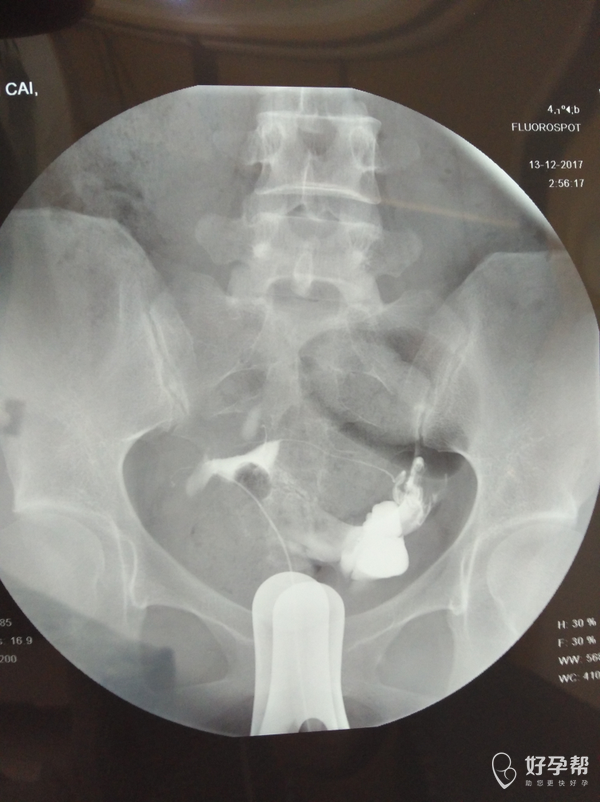

输卵管通而不畅应该怎么治疗

麻烦医生指点,输卵管通而不畅要怎么治疗?我的右侧输卵管部分切除,所有希望都寄托在这跟管上了,我不想试管,想自然怀孕,帮帮忙指点

,谢谢!从哪里看的出通而不畅的,也帮忙指点一下